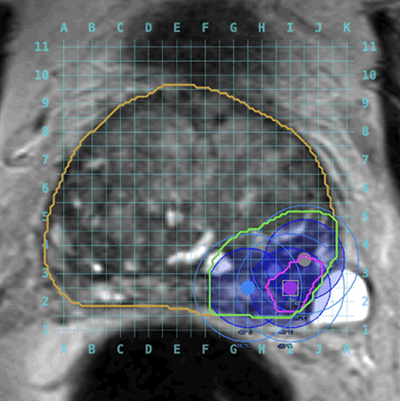

Before the procedure: Identify challenges and choose the optimal treatment modality using MR, PSMA PET Imaging, and 3D ablation energy

models.

In the operating room: Focus on executing the pre-plan.